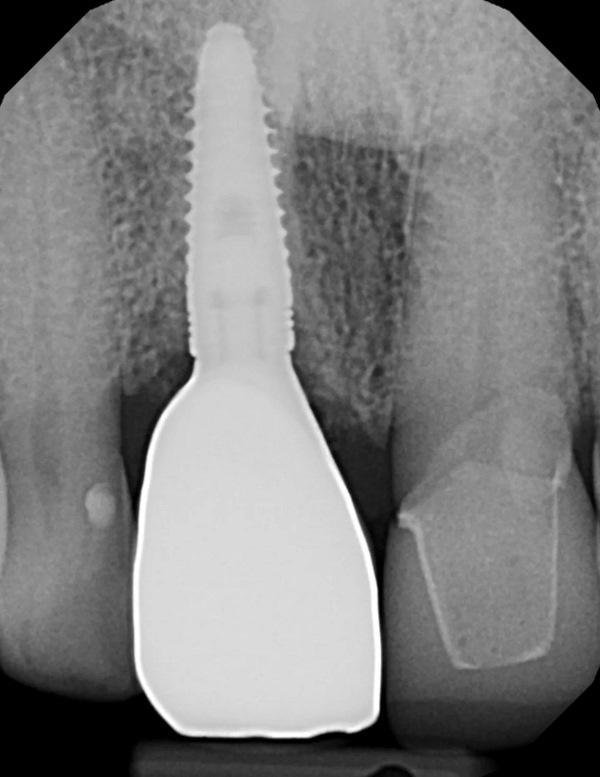

Коронка снята, канал доступа к винту в абатменте закрыт тефлоновой лентой. Коронка зафиксирована на абатменте стеклоиономерным цементом (GC FujiCEM 2, GC America). После отверждения цемента излишки по краю удалены зондом. Окклюзия проверена и при необходимости откорректирована (Фото 13). Выполнена прицельная рентгенограмма для документирования окончательной реставрации (Фото 14) и получен интраоральный скан (Primescan) для изготовления ночной каппы.

Фото 14. Прицельная рентгенограмма коронки на имплантате, зафиксированной на индивидуальном абатменте, демонстрирует уровень кости на гребне относительно уровня имплантата.

На годовом профилактическом осмотре мягкие ткани вокруг реставрации с опорой на имплантат без признаков воспаления и выглядят здоровыми (Фото 17). Выполнена прицельная рентгенограмма для контроля уровня кости на гребне (Фото 18). Гребневая кость, подсаженная при установке имплантата, сохранялась на необходимом уровне, что указывает на поддержание здоровой кости на уровне гребневой части имплантата.

Фото 18. Прицельная рентгенограмма через 1 год после фиксации реставрации демонстрирует сохранность уровня кости на гребне.